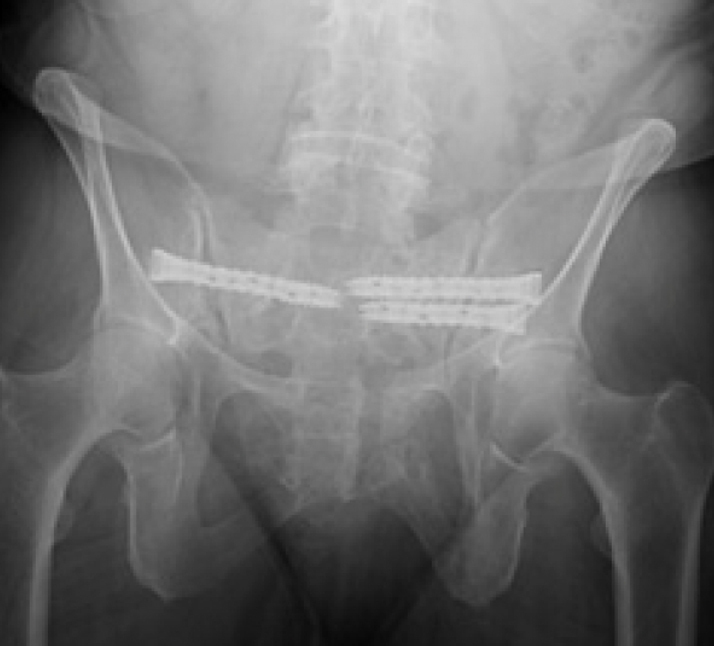

Surgical treatment:

• Bilateral sacral fracture fixation with iFuse TORQ®

Post-op:1,2

• Tolerated procedure well

• Immediate weight bearing as tolerated

• Ambulated 150 feet POD 1 and discharged home

• Pain improvement and healed fracture at 2 months

• No progression of kyphotic deformity